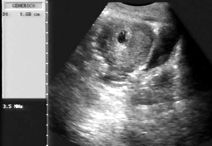

Data inserimento: 07 /11/2012Ecografia del: 31/10/2012 Strumento: Esaote MyLab 50 Gold - Responsabile Linea Cardio Esaote Regione Marche Dr. Franco Fabi Sonda: Convex Multifrequenza 2,5-5 Mhz ed Endocavitaria 5-8 Mhz Età Paziente: F 37 anni Motivazione dell'esame: ritardo mestruale. U.M. 25/09/2012. Commento all'esame: le immagini ed il video documentano il sacco gestazionale delle dimensioni di 10 mm, confermato con ecografia transvaginale (dimensioni di 9,5 x 10,6 mm), con evidenza del sacco vitellino, indice sicuro di gravidanza intra-uterina e corrisdpondente alla quinta settimana di gestazione (5 + 1). Beta-HCG = 13.302 mU/ml. Conclusioni: gravidanza alla quinta settimana di gestazione. Potete esprimere le vostre osservazioni e commenti sul BLOG. Presentazione: Dr. Massimo Dolciotti - Ancona Elaborazione digitale: Andrea Dini - Ancona